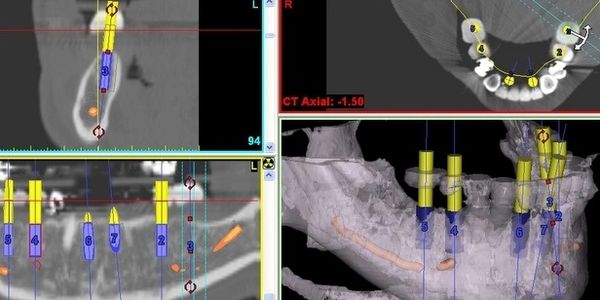

-All on 4- El primer paso es entender de forma detallada las condiciones específicas del paciente, En Dentaltek Monterrey lo hacemos con ayuda de alta tecnología y de la experiencia. Esto se hace mediante:

Una vez teniendo el plan de tratamiento con Implantes Dentales definido, el siguiente paso es realizar la prótesis provisional; El compromiso es que en ningún momento del proceso usted salga del nuestro consultorio sin dientes

En esta cita se realiza la colocación de los Implantes Dentales así como la instalación de la prótesis provisional. Todo el procedimiento es ambulatorio, se lleva a cabo en nuestras instalaciones, perfectamente acondicionadas.